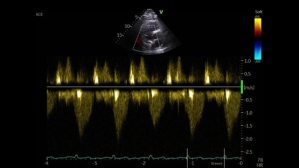

Ce patient de 86 ans est hospitalisé pour des lésions dermatologiques aspécifiques. Il présente plusieurs facteurs de risque cardiovasculaire : un tabagisme ancien, un diabète de type 2, de l’hypertension, une dyslipidémie et un surpoids. Il est également atteint d’une surdité non appareillée et d’une maladie aortique.